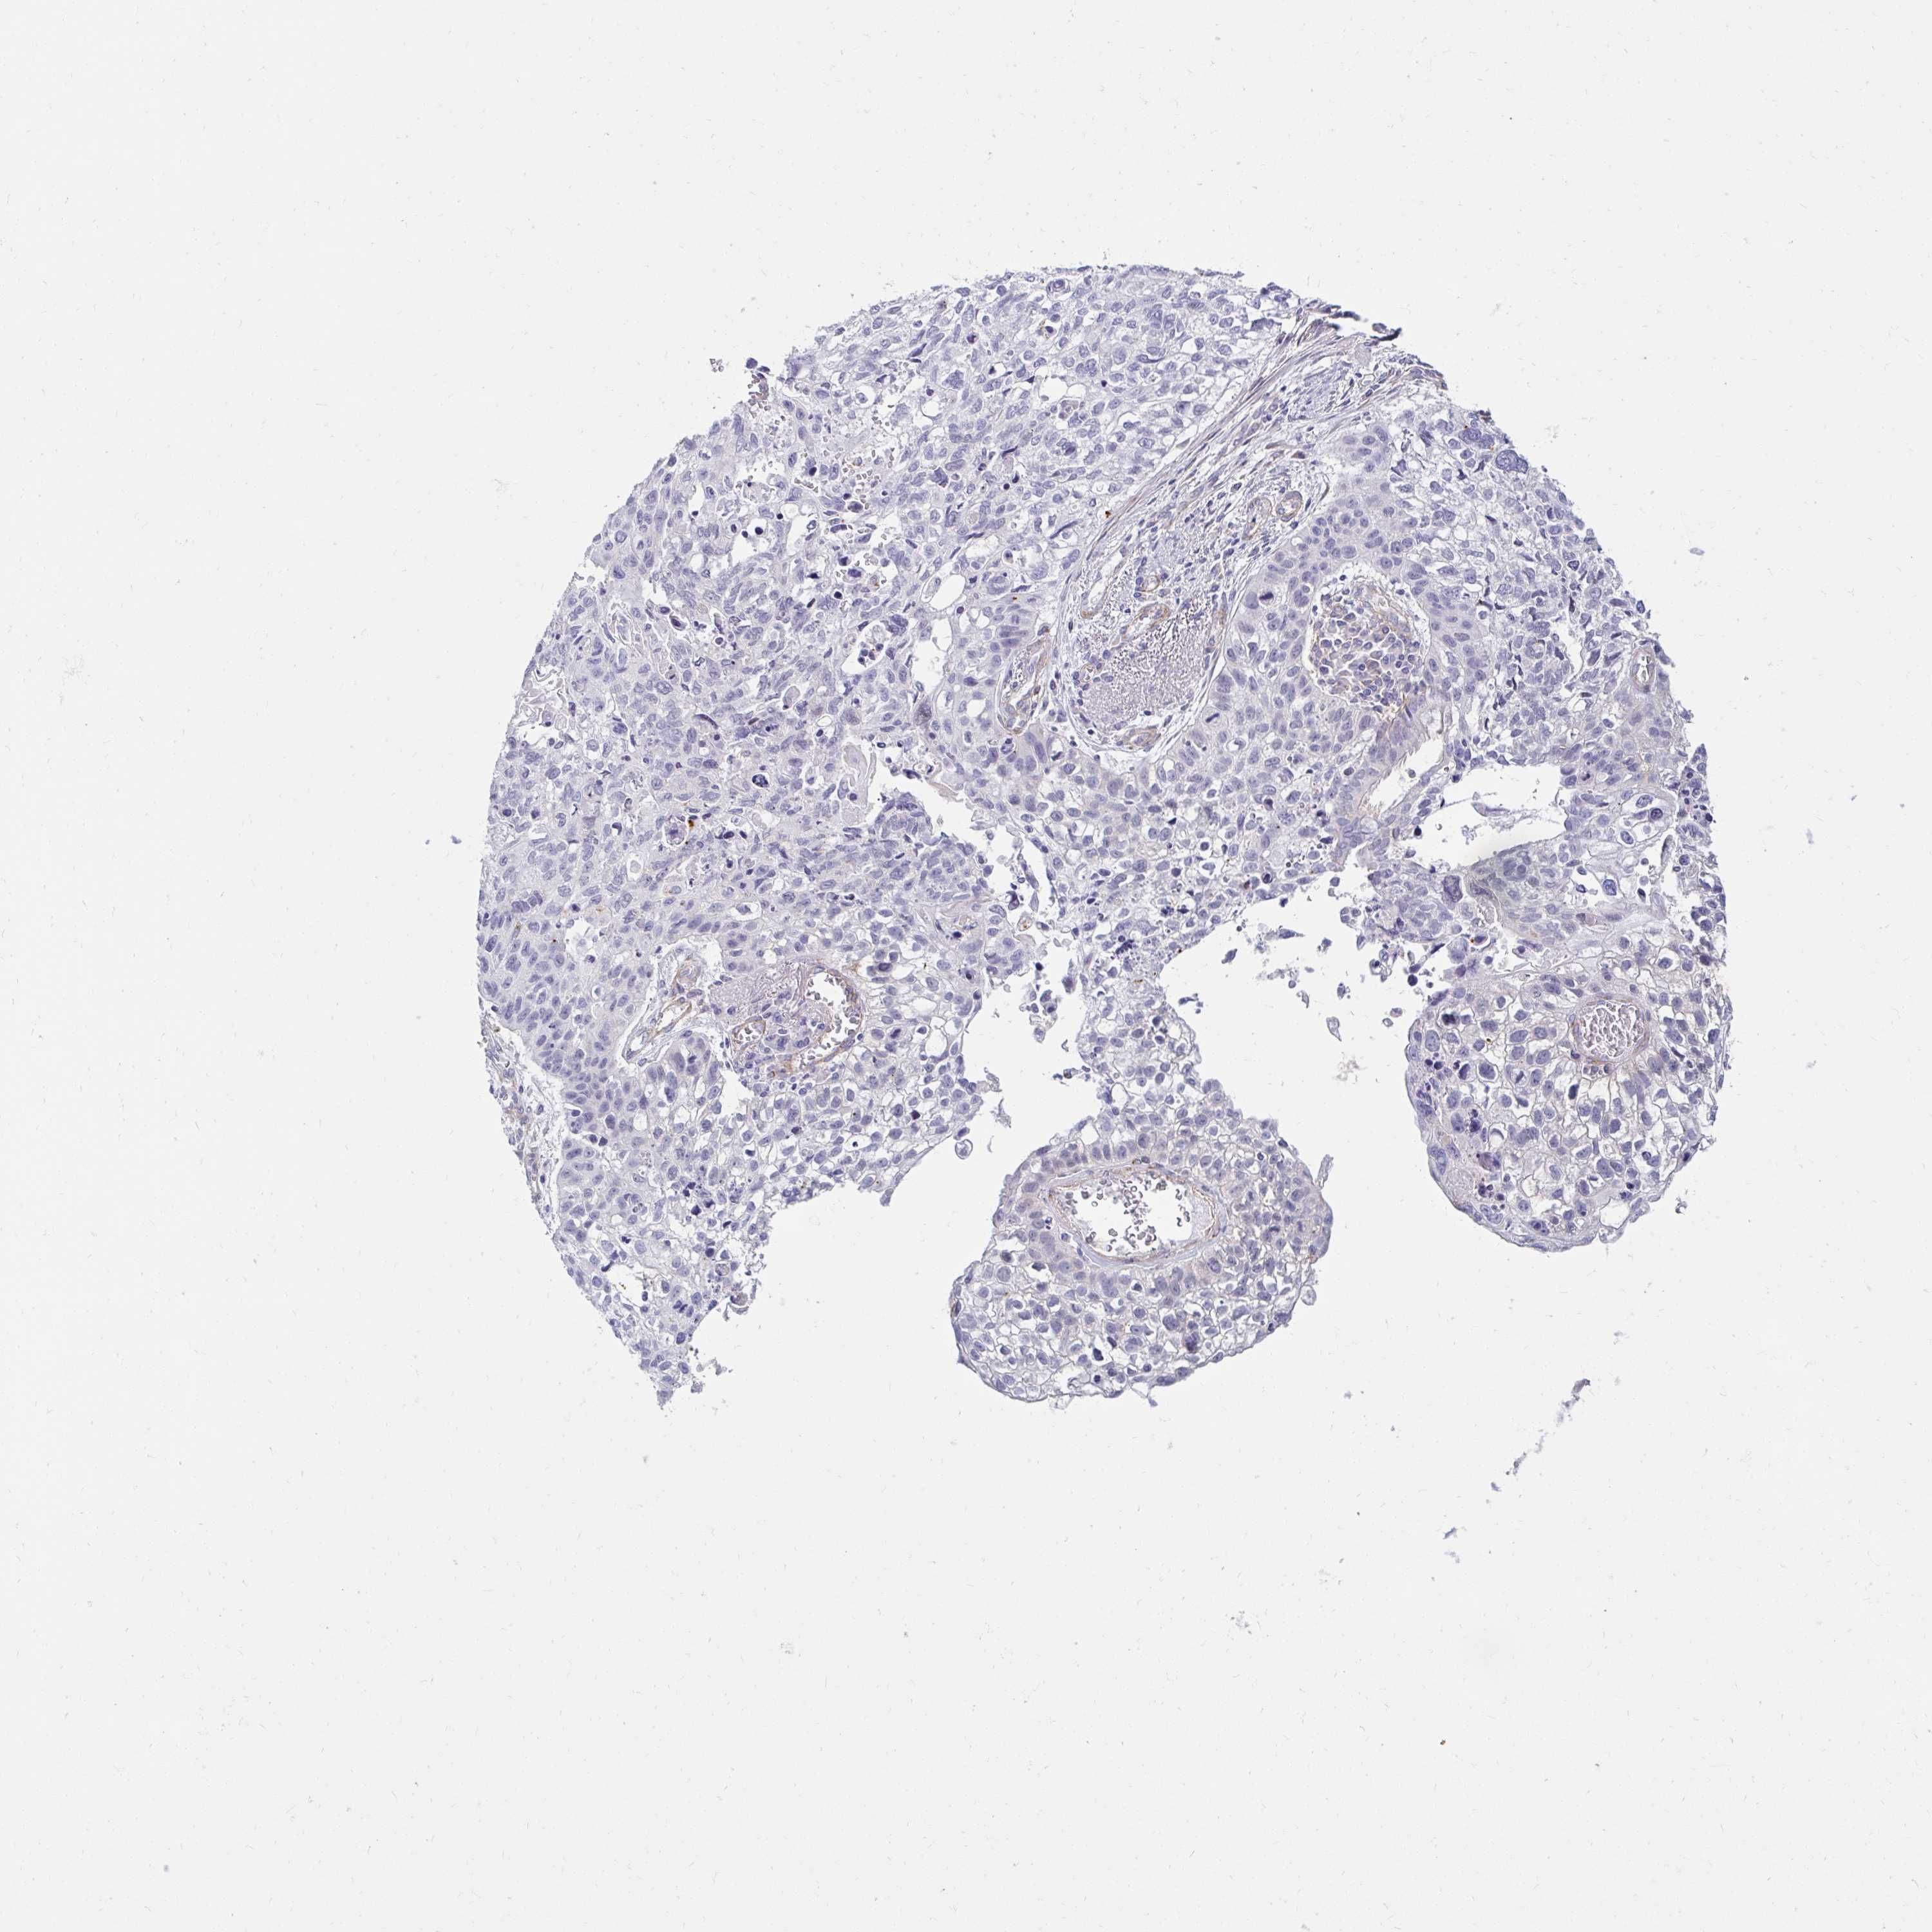

TCGA RNA samplesi

RNA-seq data is reported as average FPKM (number Fragments Per Kilobase of exon per Million reads), generated by the The Cancer Genome Atlas (TCGA) .

Normal distribution across the dataset is visualized with box plots, shown as median and 25th and 75th percentiles. Points are displayed as outliers if they are above or below 1.5 times the interquartile range. FPKM values of the individual samples are presented next to the box plot.

Average pTPM 0.1

Number of samples 489